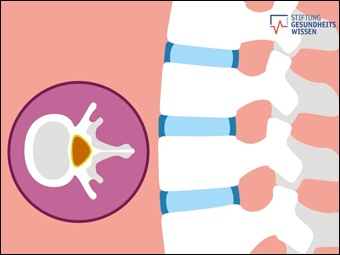

Wie funktioniert die Wirbe...

(öffentlich)

Online-Medium

(2020)